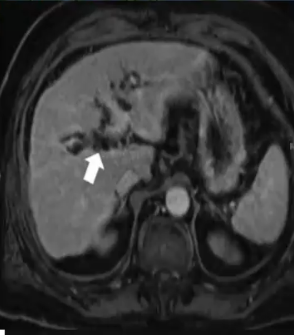

❖ 下图:胆管周围囊肿,ERCP造影无左肝胆管扩张,反而有狭窄表现